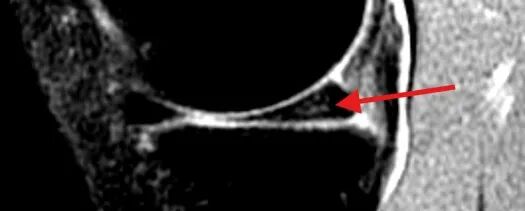

对于怀疑半月板损伤患者,应进行膝关节核磁共振(MRI)检查,该检查无创、分辨率高,对半月板损伤有很高的敏感性和特异性。根据半月板损伤的MRI表现,可以分成3级:

0 级

为正常的半月板,呈均匀的低信号,半月板形态规则。

I 级

表现为不与关节面相接触的灶性椭圆形或球形高信号。

II 级

表现为水平、线性半月板内高信号,可延伸至半月板的关节囊缘,但未达到半月板的关节面。

III 级

半月板内高信号达到上或下关节面。

I级、II级损伤通常为退变信号,不需要医学干预。III级损伤显示高信号贯通到半月板表面了,等同撕裂,一般伴随症状,需要医学干预。